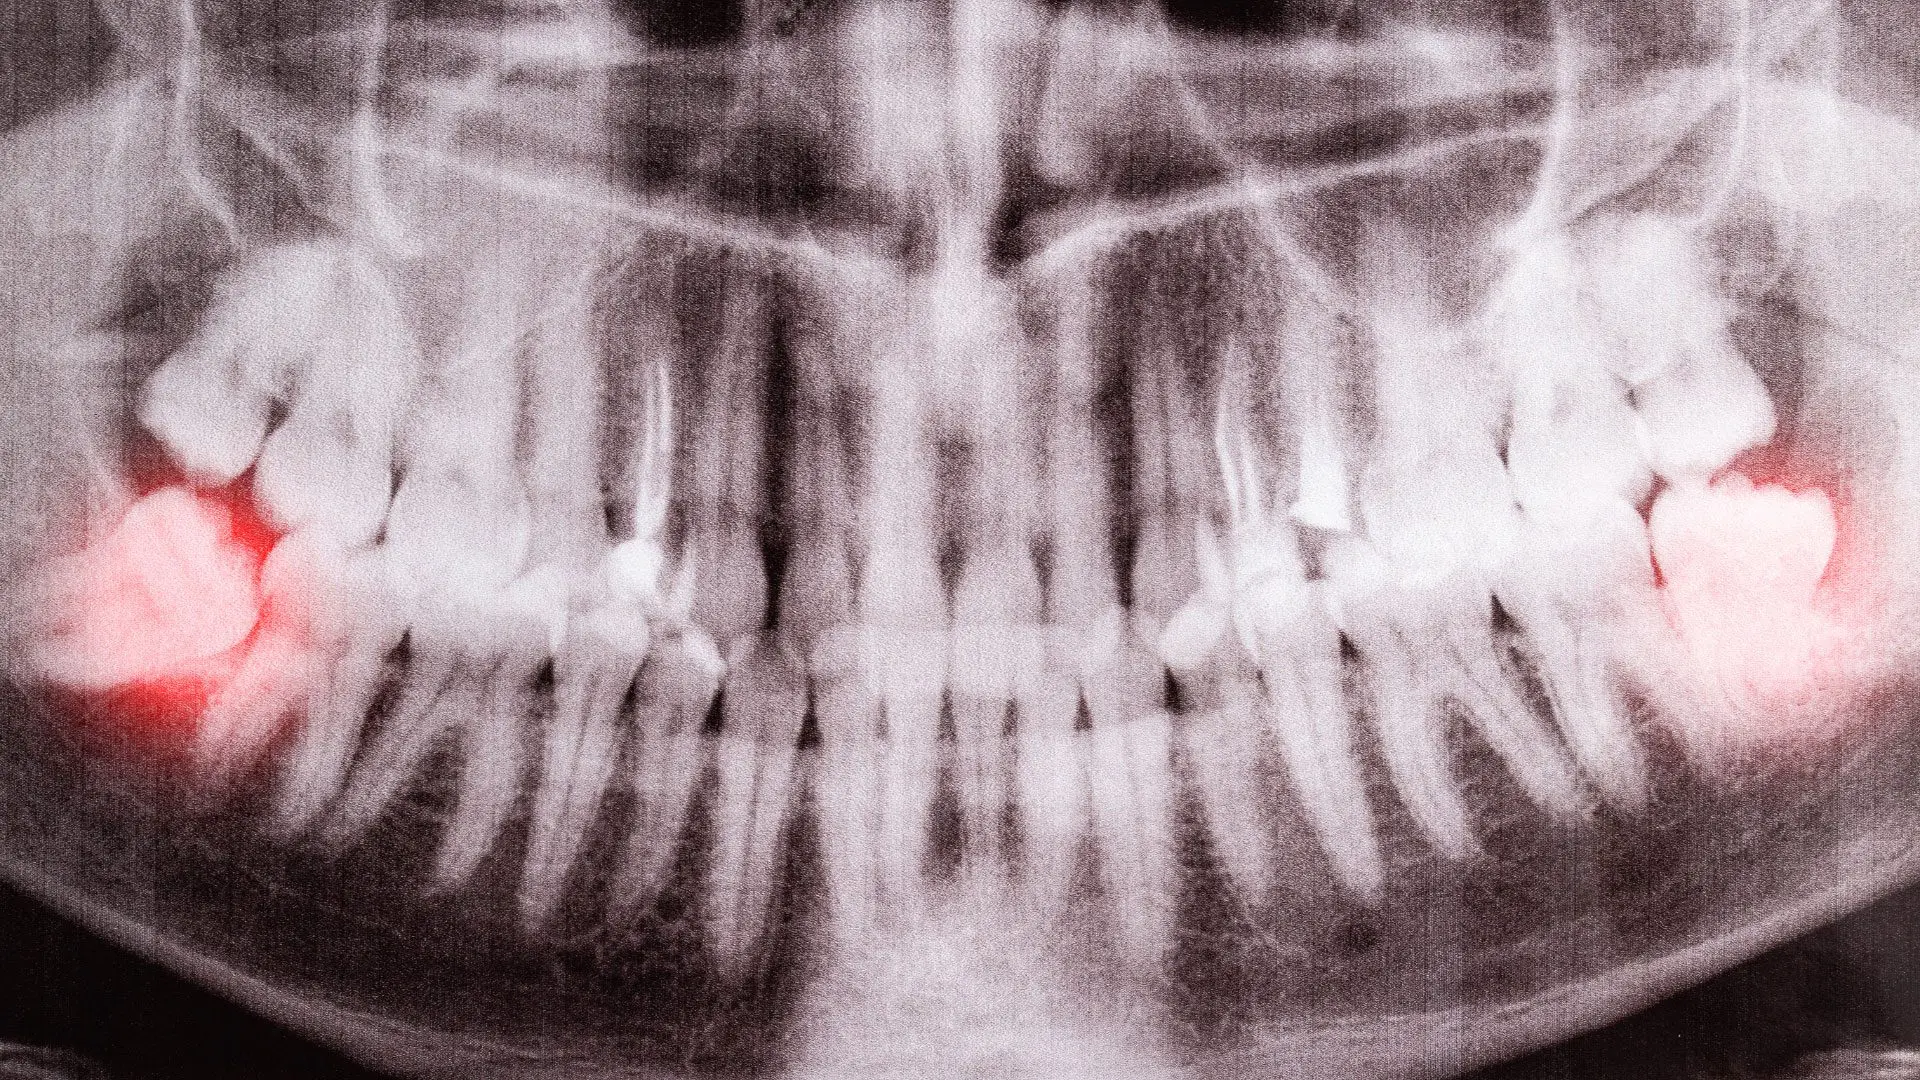

Wisdom teeth often become impacted, meaning they don’t fully emerge from the gums or grow in at an improper angle. Impacted wisdom teeth can cause discomfort, swelling, and even infection. In these cases, impacted wisdom teeth could potentially disrupt orthodontic progress or cause resorption on the far side of the second molars. Your orthodontist may recommend removing impacted wisdom teeth to prevent these issues.